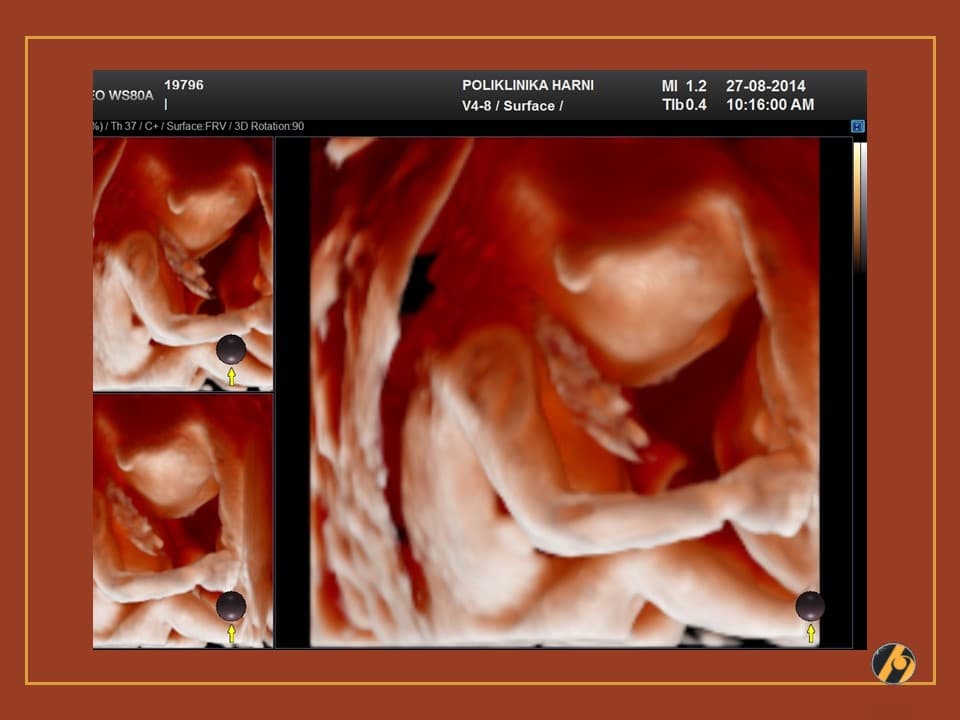

Nastavlja se finiji razvitak kože vaše bebe, koja je u ovo vrijeme tanka i prozirna i kroz koju se vidi mnoštvo krvnih žilica. Lanugo dlačice prekrivaju gotovo cijelu površinu kože bebe, a jasnije se ističu dlačice na obrvama. Počinje rasti kosa na glavi, a pigmentne stanice počinju stvarati crni pigment.

Razvijaju se daljnji centri okoštavanja i kosti, kao i koštana moždina koja preuzima funkciju žumanjčane vreće u stvaranju krvi djeteta. Zglobovi bebe su sve pokretljiviji, a beba s time i sve savitljivija. Sada vaša beba može svoje prstiće stisnuti u šaku.

Vaša beba guta amnijsku tekućinu koja ga okružuje, što pomaže sazrijevanju respiratornog sustava. Bebine oči su i dalje zatvorene, ali beba počinju reagirati na svjetlost izvan vaše maternice. Od ovog tjedna vaše će dijete početi čuti zvukove u vašem tijelu, poput otkucaja srca i trbuha.

Vaša beba dugačka je 10 - 12 cm, a teška 50 - 100 g.